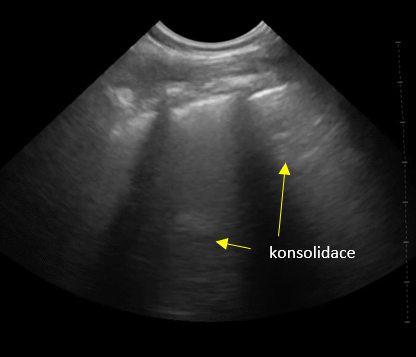

Obr. 1.3. „Bílá plíce“, alveolární syndrom, konsolidace v parenchymu.

Obr. 1.5.Konsolidace plicní tkáně s bronchogramem, malé množství výpotku nad bránicí, C linie.

V subpleurálně uložených a zejména v dorzobazálních plicních konsolidacích může být vidět dynamický bronchogram. B linie, které nezačínají na pleurální linii, ale hlouběji, za konsolidovaným plicním parenchymem bývají také nazývány linie C.